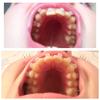

Фото НЧ до установки:

Любимая моя НЧ)

Фото НЧ сегодня(через 2 дня после установки):